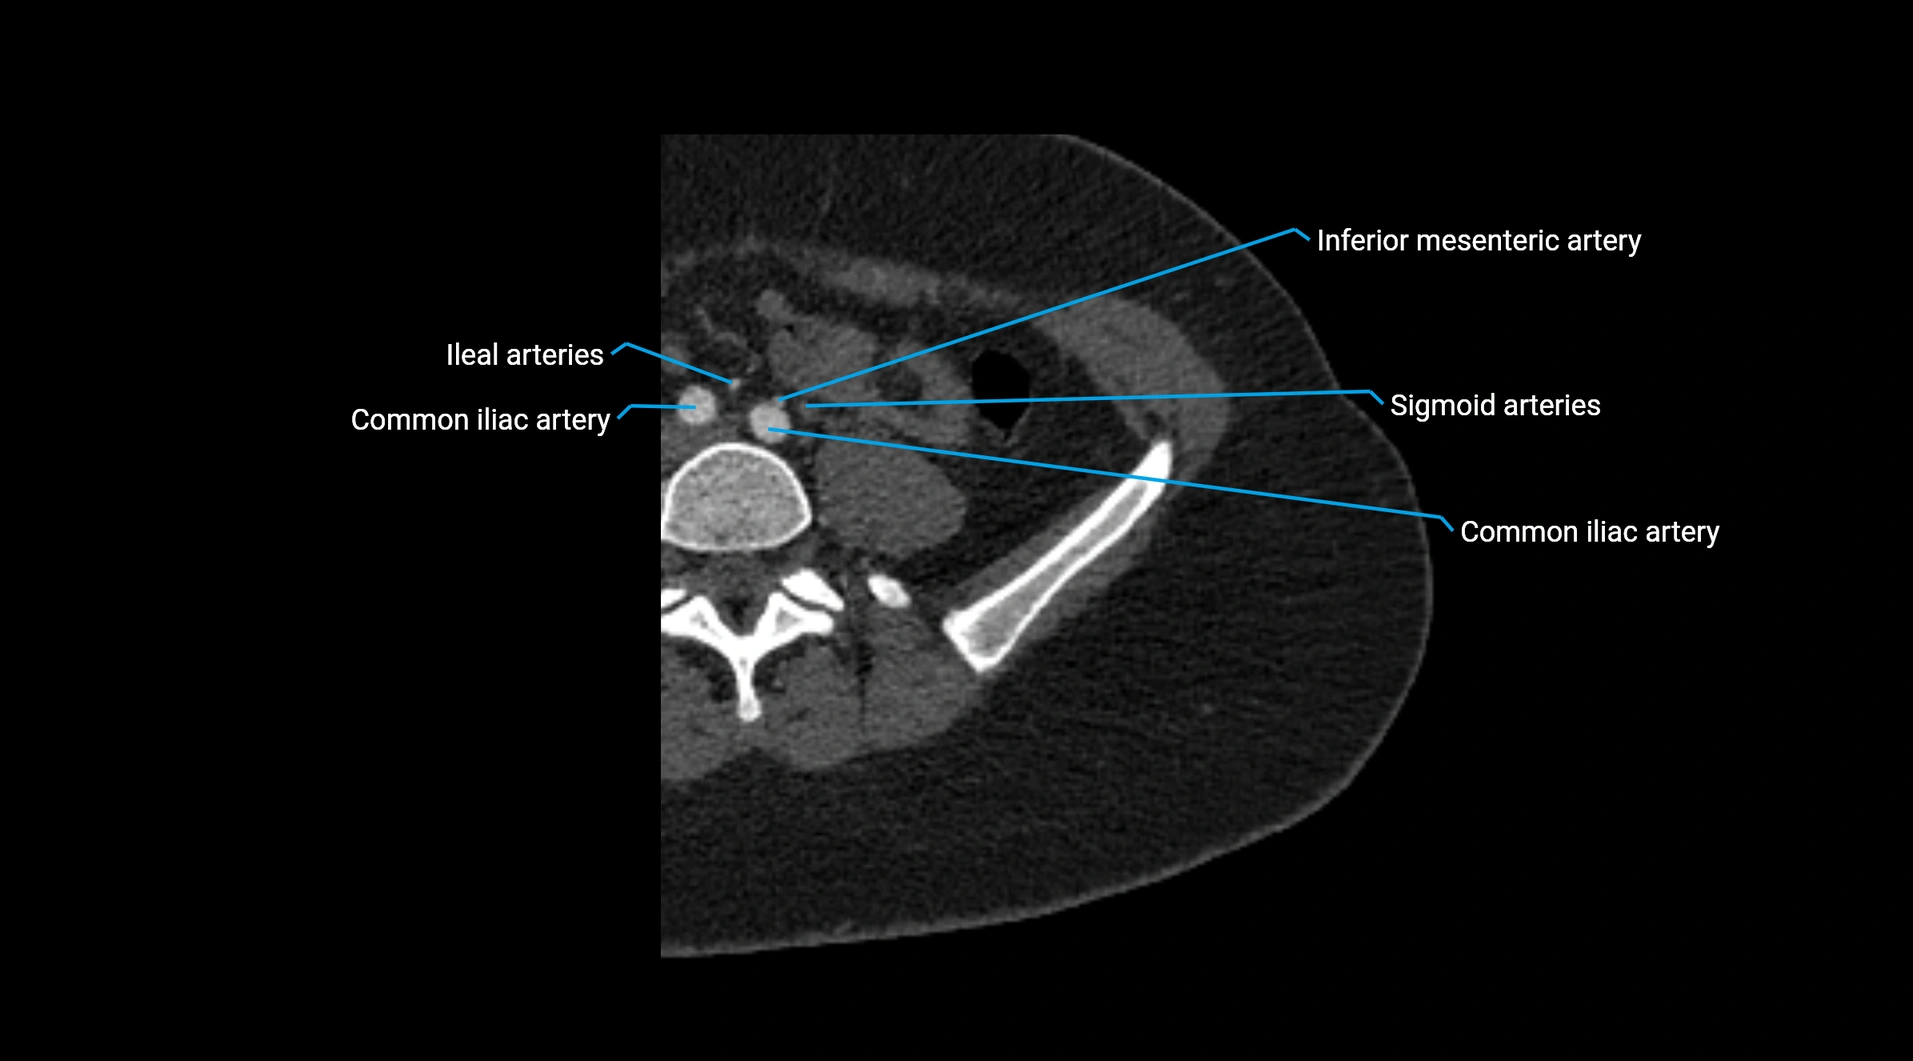

Contrast-enhanced CT (CTA):

• Gold standard for abdominal aortic imaging

• Provides excellent detail of lumen, wall, aneurysm, thrombus, and branch vessels

• Multiplanar and 3D reconstructions help in aneurysm measurement, stent graft planning, and dissection evaluation

• Detects acute rupture, traumatic injury, or occlusion with high sensitivity